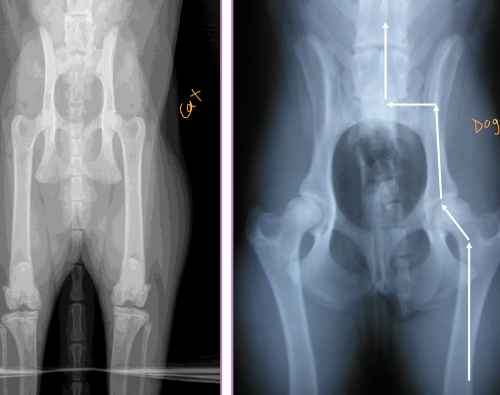

Pelvis Fractures

Considerations: Multi physes, normally breaks at multi sites

Sciatic n.: through ischiatic notch

Weight transfer: paw → tibia → femur → acetabulum → ilium → SI joint

Et: males > females, trama

Dt: Rads, CT for complex fractures/Sx planning

Tx:

Rx: non-displaced, unilateral, non-articular, non-weight-bearing fractures

6 w crate rest, sling, pain control, controlled walks, PT

Sx: ilium/acetabulum/SI joint (weight-bearing), bilateral fractures, displacement, colon compromise, pelvic canal compromise (parturition), sciatic entrapment

Ilium: plate + screws

Acetabulum: plate + screws, cross pins, PMMA

SI joint: screw stabilization